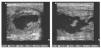

El 15 de noviembre de 2006 inició un cuadro de molestias en la región deltoidea derecha, sin antecedente traumático, con dolor a la palpación, enrojecimiento y calor local. Se encontraba afebril y no presentaba malestar general. Se realizó ecografía, en la que se observa colección anecoica extensa de 5 × 10 cm en el músculo deltoides derecho compatible con absceso muscular (fig. 1).

Figura 1 Imagen anecoica de bordes bien delimitados compatible con absceso muscular en deltoides.